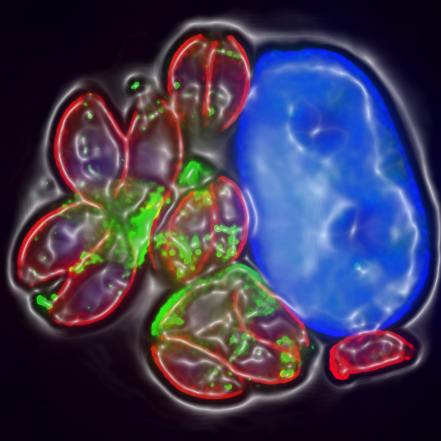

Pictured:  A Toxoplasma-infected human cell moments before it bursts (WEHI)

The researchers showed that the parasites were able to lay dormant and undetected inside neurons (brain cells) and muscle cells by releasing proteins that switch off the cells’ ability to alert the immune system. With expertise and technologies from WEHI’s Advanced Genomics facility and Centre for Dynamic Imaging, they were able to visualise the parasites in real-time.